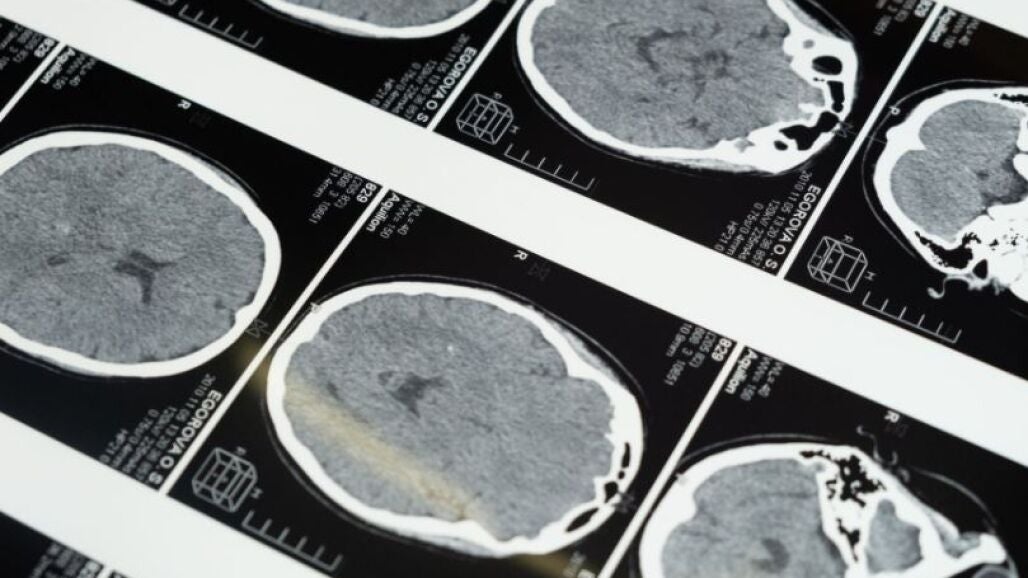

Para atender esta patología, que puede dejar graves secuelas en las personas que la sufren, el complejo hospitalario Ruber Juan Bravo impulsó hace más de cinco años: la Unidad de Ictus, un servicio de carácter urgente al Hospital Universitario Quirónsalud Madrid, al Hospital la Luz y al Hospital Quirónsalud Sur.

Y es que el Dr. Arroyo subraya que «la atención inmediata es esencial para mejorar el diagnóstico y reducir el riesgo de secuelas, por lo que aseguramos una asistencia urgente las 24 horas en los cuatro centros que integran la unidad. Así como un innovador sistema de Teleictus permite al neurólogo atender por teleconferencia y en tiempo real al paciente en cualquiera de los hospitales».